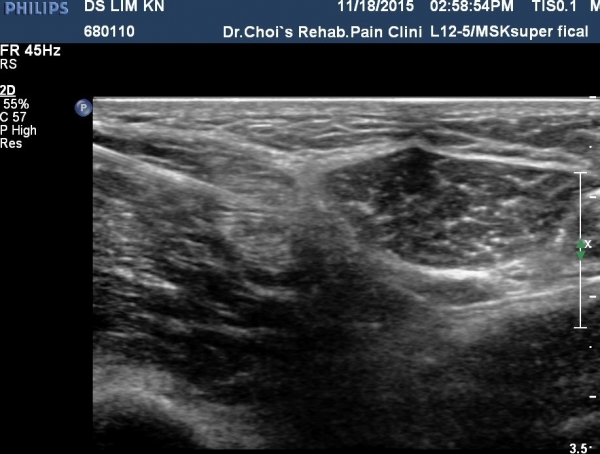

ÃÊÀ½ÆÄ À¯µµÇÏ(»çÁø 5)¿¡ ½½°üÀý ºÐÁö ½Å°æÂ÷´Ü¼úÀ» ½ÃÇàÇÔ(»çÁø 4, ÷ºÎ µ¿¿µ»ó).

º¹Àç½Å°æ ½½°í³ªÀýºÐÁö Â÷´Ü¼ú(»çÁø 4, 5, ÷ºÎµ¿¿µ»ó)

ÃÊÀ½ÆÄ·Î º¸Àç½Å°ÜÀ» °üÂûÇÏ¿© º¹Àç½Å°æÀÌ ½½°üÀýºÐÁö¿Í ¸»´Ü°¡Áö·Î ºÐ¸®µÈ ÈÄ ½½°üÀýºÐÁö¿¡

½Å°æÂ÷´Ü¼úÀ» ½ÃÇàÇϸé Â÷´Ü¼ú ÈÄ ¾Æ·§´Ù¸®¿¡ ¹ß»ýÇÒ ¼ö ÀÖ´Â °¨°¢ÀÌ»óÀ» ¿¹¹æÇÒ ¼ö ÀÖ´Ù.